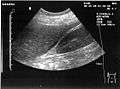

Ultrasound of liver (left side of the image) and right kidney (right side of the image) and Morison's pouch, not containing fluid.- Abdominal CT, showing Morison's pouch as the dark margin surrounding the right kidney (at lower left corner of image).